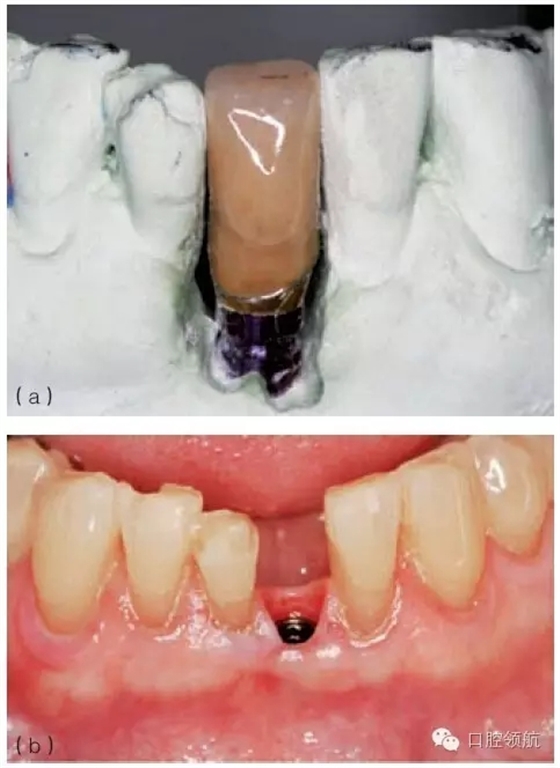

牙周探診是測量種植體周邊牙齦深度的最佳方式。探診深度源于軟組織的厚度。如果由于厚牙齦導(dǎo)致探診過深,且種植體未位于美學(xué)區(qū)域內(nèi)時,可以通過外科手術(shù)削薄牙齦組織,以獲得較淺的袖口。但是,如果這種處理導(dǎo)致明顯的軟組織缺陷,就應(yīng)該保留這種深的袖口??上鄳?yīng)地采用長穿齦高度的基臺,來彌補厚牙齦的問題(圖9.25 a,b)。然而,因為種植體周較深的探診深度,導(dǎo)致個人及專業(yè)的衛(wèi)生維護困難,使炎癥(黏膜炎)的幾率增大。因此,必須告訴患者維護好這些區(qū)域,并定期監(jiān)測。

圖9.25 (a)臨床檢查可見軟組織過厚、基臺過短、固位不佳,因此牙冠反復(fù)脫落。(b)臨床檢查可見,穿出牙齦的基臺高度足夠,可以滿足粘結(jié)固位的要求。